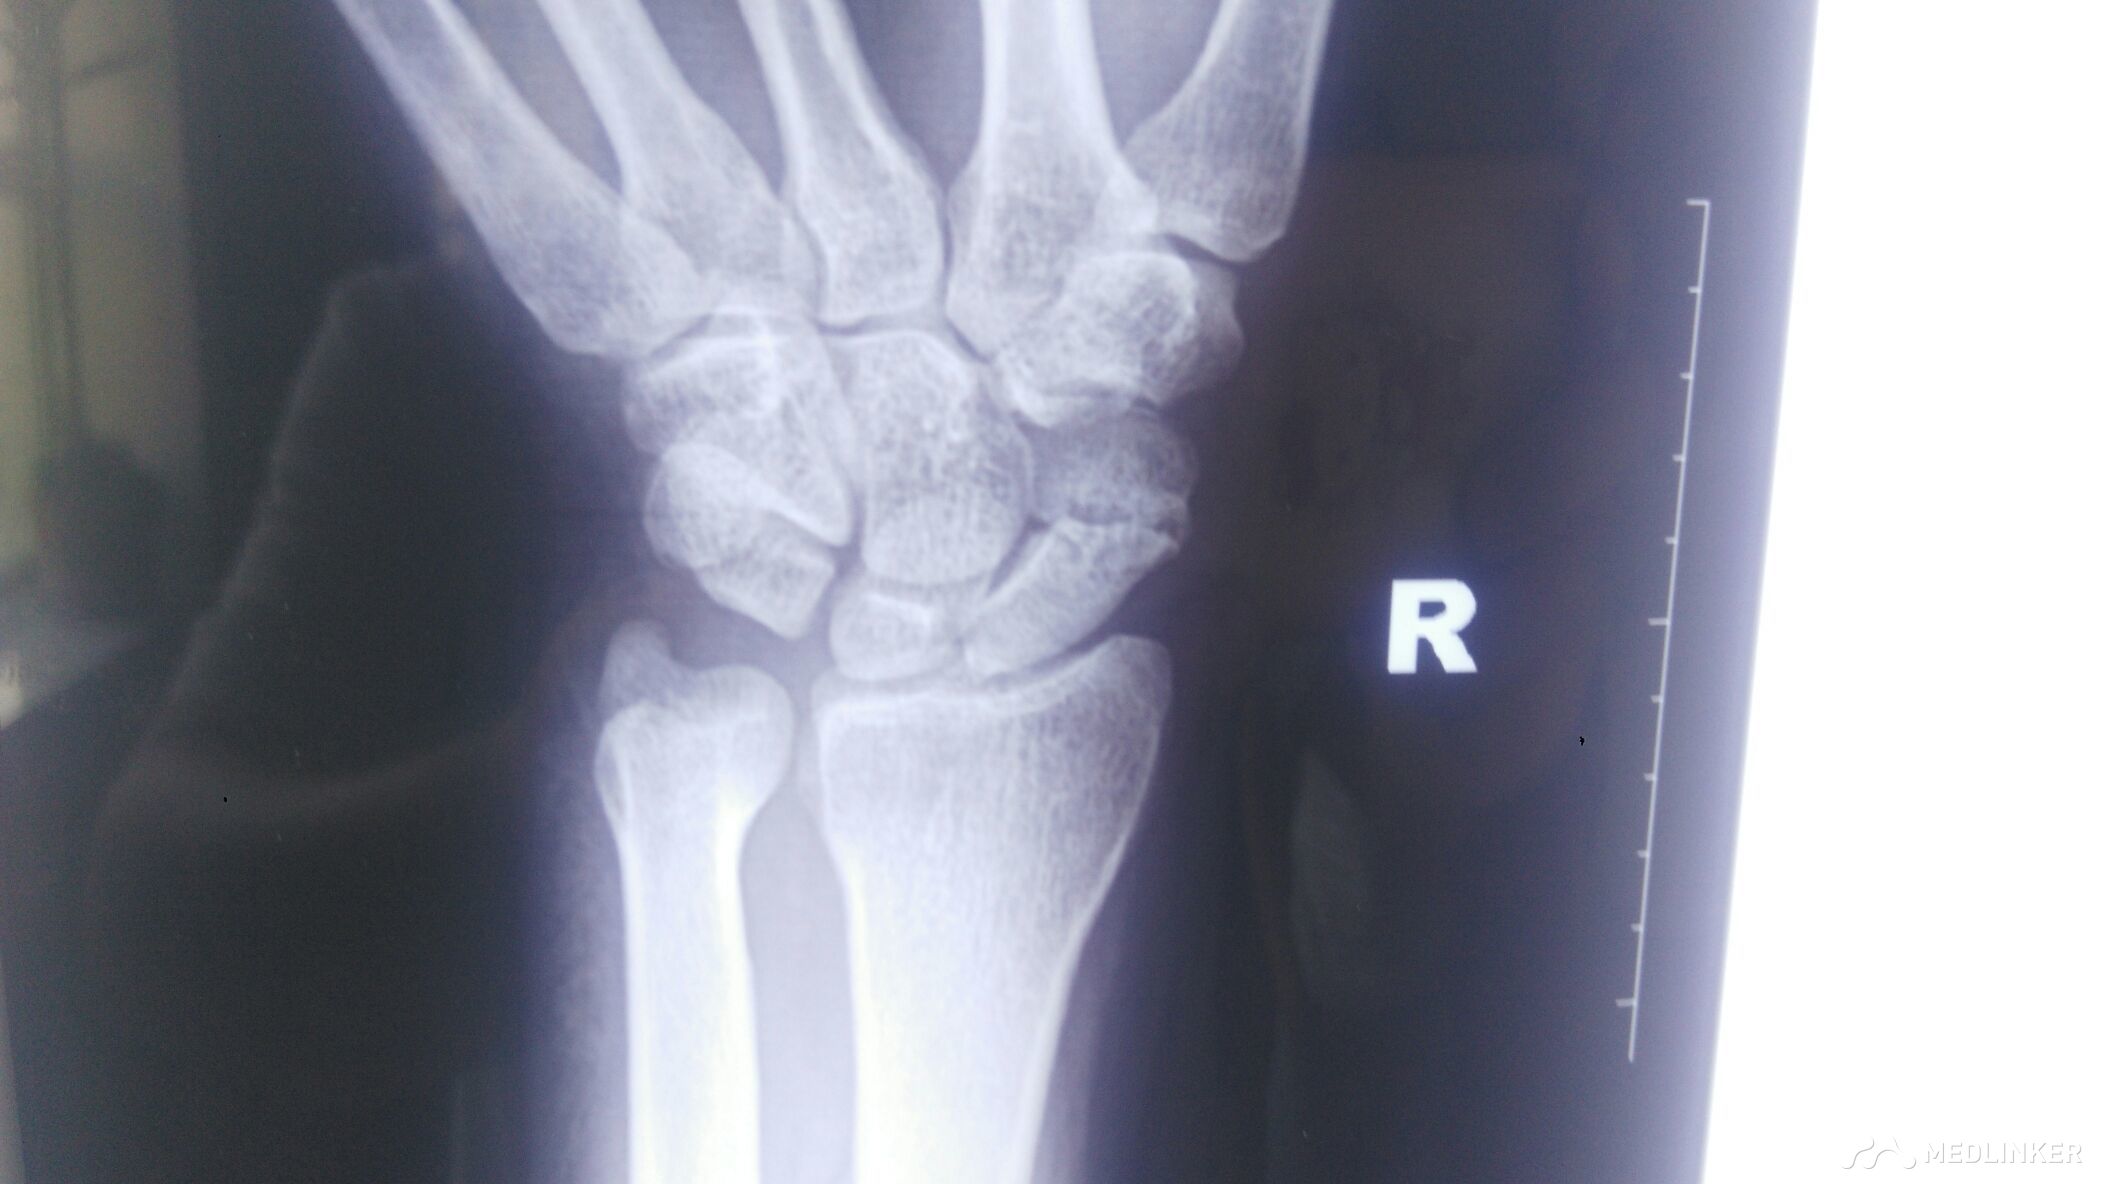

右侧舟状骨陈旧性骨折。

右腕部外伤后,未重视,未治疗。今日来拍片子。右侧腕关节活动受限伴疼痛。

右腕部外伤后4月,右腕部,鼻咽窝处压痛阳性,叩痛阳性,右腕部关节活动受限。

右侧舟状骨陈旧性骨折,手术治疗。

手术治疗后,腕部骨折可以愈合,但是,腕部活动后遗症疼痛有好的办法吗?